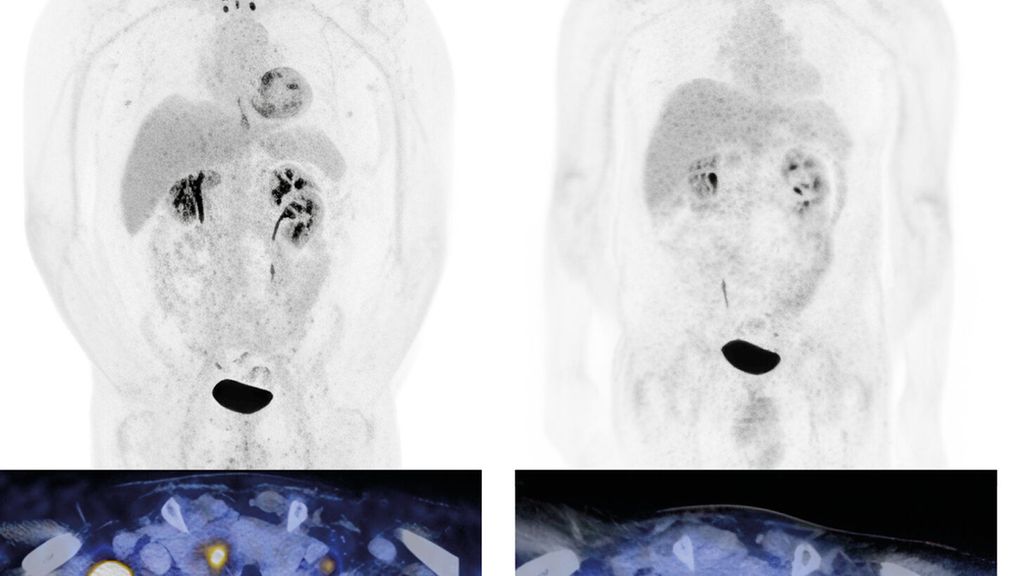

Fig.1: Carcinome urothélial de la vessie (initialement cT3 cN3 cM0) avec métastases lymphogènes métachrones. Classification par tomodensitométrie (TDM) avec diagnostic de métastases lymphogènes (a, à gauche). Première reclassification deux mois après le début du traitement par EV+P (b, à droite). L’image montre une rémission complète. Le patient est toujours en rémission durable. Images et patient de l’Hôpital universitaire de Zurich